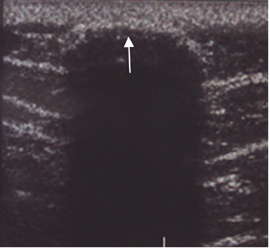

Fig 210A. Calcificación.

Ecografía. Imagen ecogénica y superficial que produce sombra acústica.

Corresponde a calcificación inespecífica de los tejidos blandos.